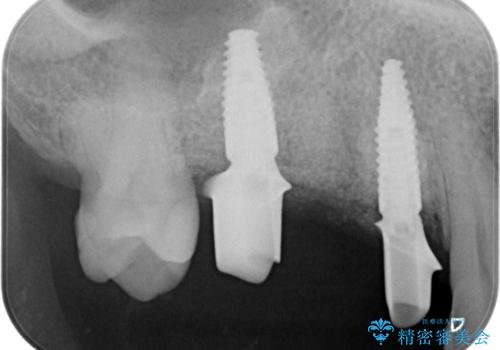

3本の歯が失われた状態を、2本のインプラントで支えるブリッジでの咬合機能回復を計画します。

- 150万円(インプラント×2・チタンカスタムアバットメント×2・ジルコニアクラウン×3・仮歯×3)費用は治療当時の料金となります